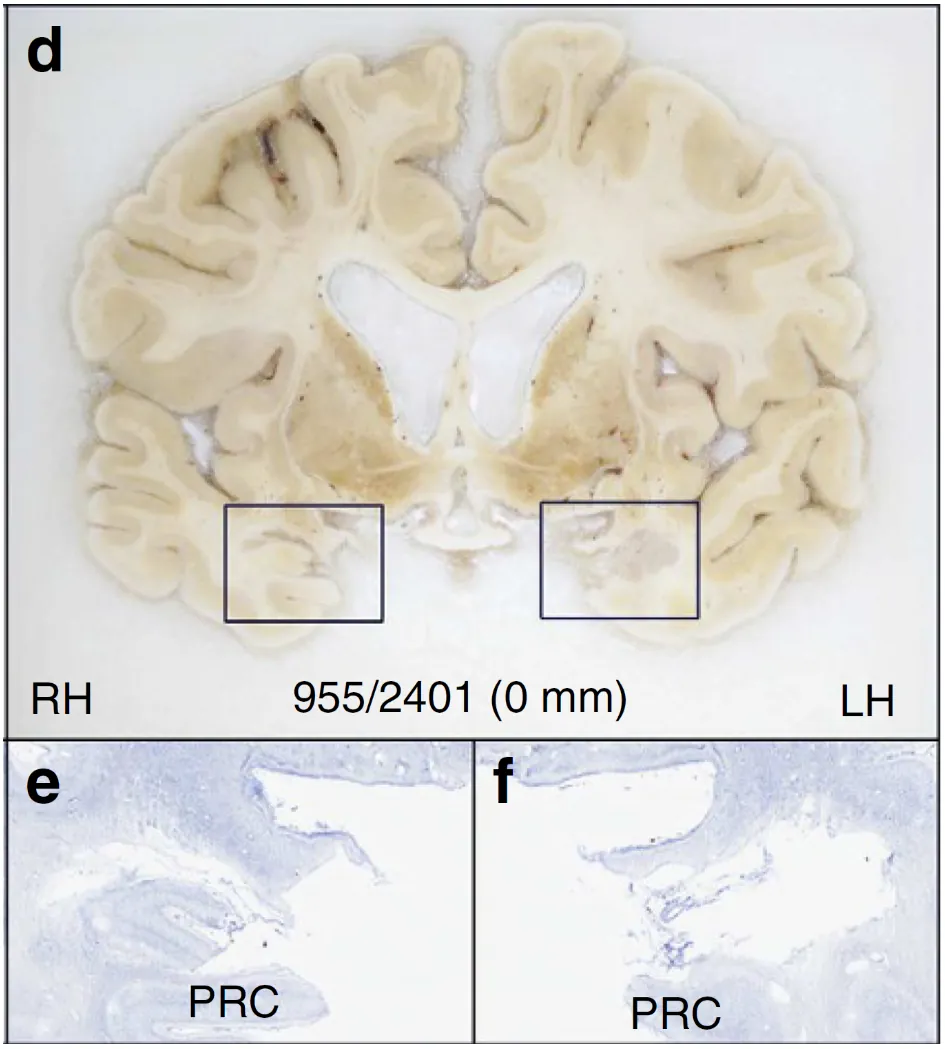

Photo of postmortem coronal brain slice from HM, showing loss of tissue where hippocampus should be.

Figure 18.4 H.M. Images of H.M.'s brain show large portions of the hippocampus is missing. Counterstaining of the sections in boxes on the top are shown on the bottom. Image credit: Annese, J., Schenker-Ahmed, N., Bartsch, H. et al. Postmortem examination of patient H.M.’s brain based on histological sectioning and digital 3D reconstruction. Nat Commun 5, 3122 (2014). https://doi.org/10.1038/ncomms4122. CC-NC-ND 3.0